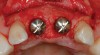

Figure 15  After extraction and 3 months of healing, two implants were placed in ideal position and with primary stability at sites Nos. 8 and 9. Implants were stable. Dehiscence defects exposing 13 threads were produced.

Figure 15

Figure 20  At the second-stage surgery following a healing period of 5 months, temporary healing abutments were placed. This occlusal view shows complete regeneration of the labial plate of bone.

Figure 20